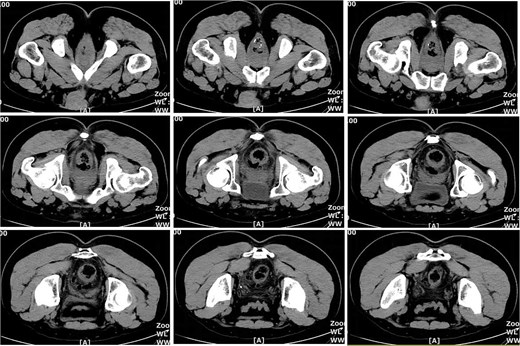

On postoperative Day 15, a complete blood count showed a white blood cell count of 9.12 × 109/l and a neutrophil percentage of 77.5%. Pelvic CT demonstrated rectal wall edema, anterior wall perforation, and partial absorption of the surrounding infection, indicating reduced infection severity compared to the previous scan on postoperative Day 10 (Fig. 3). Given the patient’s satisfactory response to antibiotic therapy and absence of ongoing infection signs, intravenous antibiotic treatment was discontinued.